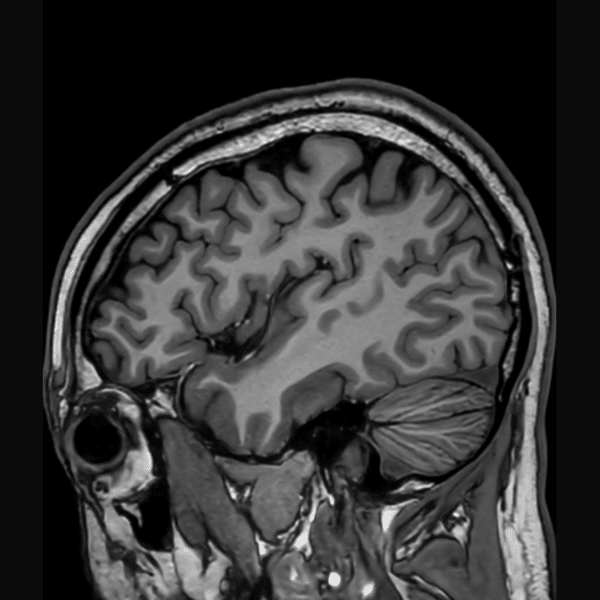

Brain 3D T1WI

3.0T Philips Ingenia CX

3D TFE

(L) 1.0×1.0x1.0 mm

(R) 0.8×1.1×1.1 mm

Conventional SwiftMR™ 03:14 02:07 (35% Faster)